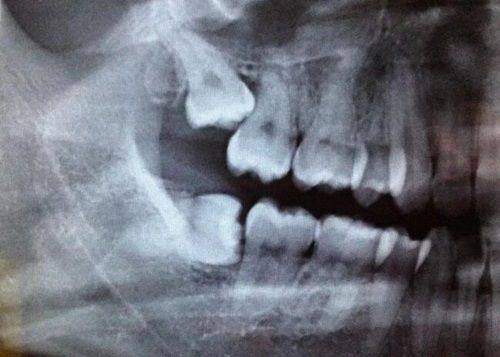

该分院的特色服务是儿童早期矫治和儿牙预防保健。儿童早期矫治能够在孩子牙齿和颌骨发育的关键时期进行干预,引导牙齿和颌骨的正常生长,避免后期出现更重度的牙齿问题。儿牙预防保健则注重培养孩子良好的口腔卫生习惯,通过定期检查、涂氟、窝沟封闭等措施,有效预防龋齿等口腔疾病的发生。家长们对该店的儿童齿科服务表示非常满意,认为医生们能够良好地安抚孩子的情绪并顺利完成治疗。特别多孩子原本对看牙充满恐惧,但在医生的耐心引导下,都能积极配合治疗。

星斓荟店提供儿童牙齿护理、牙齿矫正等多项服务,帮助孩子从小养成良好的口腔卫生习惯。儿童牙齿护理包括日常的口腔清洁指导、牙齿检查等,让孩子们了解正确的刷牙方法和口腔护理知识。牙齿矫正则针对不同年龄段的孩子,采用合适的矫正方法,如早期功能性矫正、固定矫正等,改善孩子的牙齿排列和咬合问题。家长们对这里的服务也赞不绝口,他们表示医生非常专精,服务态度也好,治疗过程非常舒适,孩子们也非常喜欢这里。医生们会根据每个孩子的具体情况制定个性化的治疗方案,确保治疗成效的同时,也让孩子在治疗过程中感受到舒适和关怀。